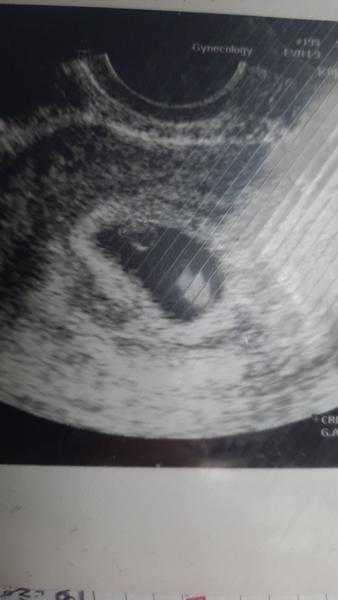

@piggy123 ted jdu od doktorky byla tam dutinka a gestacni vacek pristi patek jdu znova dala mi neschopenku ze nemám chodit mezi lidi. Tak snad uz bude vse ok.😘

@piggy123 ahoj tak jsme po kontrole jsem 6+0 srdíčko bije tak snad uz bude vse jak má 🙏🍀❤